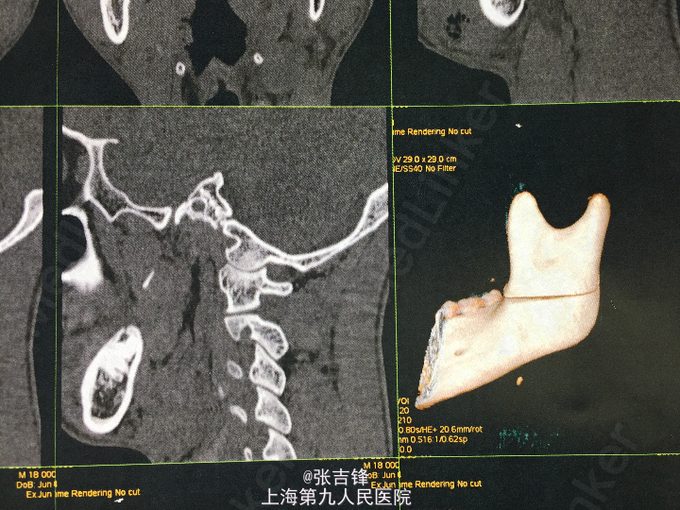

神志清楚,左面颊部长约10cm开放性创口,深达骨面,活跃性出血,可见下颌升支横行骨折,异常动度,腮腺破损,腮腺导管断裂,张口度2cm,咬合关系尚可,口角无偏斜,左侧鼻唇沟变浅。 CT:左侧下颌升支骨折

诊断:左侧面颊部软组织刀砍伤,下颌升支骨折,腮腺腺体损伤导管断裂,面神经下颊支断裂 处理:急诊止血后做头颅及下颌骨CT,完善术前检查,全麻下行“左侧下颌升支骨折内固定,腮腺导管吻合,破损腺体缝扎,面神经下颊支吻合及软组织清创缝合术

术后恢复良好,创口I级愈合,腮腺导管通畅,咬合关系良好,张口度3.0cm 讨论:开放性骨折如机体允许情况下宜一期行内固定术,避免二次创伤,腮腺导管断裂需吻合,腮腺腺体破损需严密缝合以防涎漏,面神经分支断裂需吻合。